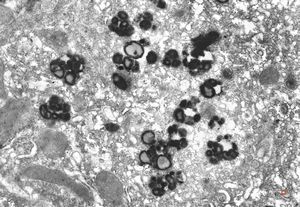

F,32y. | M. Gaucher